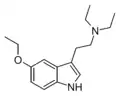

| 5-Ethoxy-DMT | artificial | 5-OCH2CH3 | CH3 | CH3 | 5-ethoxy-N,N-dimethyltryptamine | 855245-09-9 |

| 5-Ethoxy-MET | artificial | 5-OCH2CH3 | CH3 | CH2CH3 | 5-ethoxy-N-methyl-N-ethyltryptamine | |

| 5-Ethoxy-DET | artificial | 5-OCH2CH3 | CH2CH3 | CH2CH3 | 5-ethoxy-N,N-diethyltryptamine | |

| 5-Ethoxy-MPT | artificial | 5-OCH2CH3 | CH3 | CH2CH2CH3 | 5-ethoxy-N-methyl-N-propyltryptamine | |

| 5-Ethoxy-EPT | artificial | 5-OCH2CH3 | CH2CH3 | CH2CH2CH3 | 5-ethoxy-N-ethyl-N-propyltryptamine | |

| 5-Ethoxy-DPT | artificial | 5-OCH2CH3 | CH2CH2CH3 | CH2CH3 | 5-ethoxy-N,N-dipropyltryptamine | |

| 5-Ethoxy-MiPT | artificial | 5-OCH2CH3 | CH3 | CH(CH3)2 | 5-ethoxy-N-methyl-N-isopropyltryptamine | |

| 5-Ethoxy-EiPT | artificial | 5-OCH2CH3 | CH2CH3 | CH(CH3)2 | 5-ethoxy-N-ethyl-N-isopropyltryptamine | |

| 5-Ethoxy-DiPT | artificial | 5-OCH2CH3 | CH(CH3)2 | CH(CH3)2 | 5-ethoxy-N,N-diisopropyltryptamine | |

| 5-Ethoxy-DALT | artificial | 5-OCH2CH3 | H2C=CH-CH2 | H2C=CH-CH2 | 5-ethoxy-N,N-diallyltryptamine | |